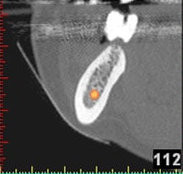

Auf Basis einer computertomografischen (CT-) Kieferaufnahme ist eine dreidimensionale Darstellung der Knochen möglich. Der Zahnarzt kann dann am Computerbildschirm die Knochenqualität (z. B. Knochendichte) beurteilen und die optimale Position der Implantate im Vorfeld planen. Durch Verwendung spezieller Röntgenschablonen lässt sich auch die erwünschte Zahnstellung in die Planung einbeziehen. Die Simulation der OP erlaubt, das zu erwartende Ergebnis mit größtmöglicher Sicherheit vorherzusagen und dem Patienten am Bildschirm zu veranschaulichen.

(siehe Bild 3 und 4).

Mit diesen gewonnenen Informationen und Planungen stellt der Zahnarzt interaktiv spezielle Bohrschablonen her. Diese ermöglichen eine exakte Positionierung der Implantate, so wie vorher am Computer geplant.